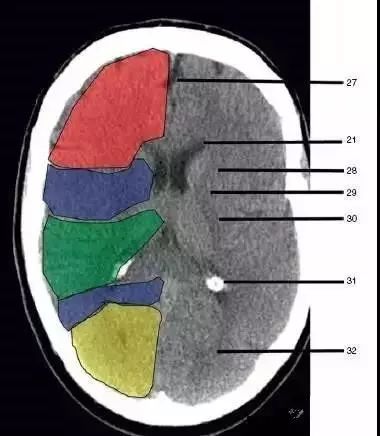

27、纵裂(Interhemispheric fissure)

28、内囊前肢(Anterior limb of internal capsule)

29、内囊膝部(Genu of internal capsule)

30、内囊后肢(Posterior limb of internal capsule)

31、侧脑室三角区及脉络丛钙化(Trigone of lateral ventricle and calcified choroid plexus)

32、侧脑室枕角(Occipital horn of lateral ventricle):绿色部分为颞叶(Temporal Lobe),浅红色部分为额叶(Frontal Lobe),黄色部分为枕叶(Occipital Lobe),褐色部分为顶叶(Parietal Lobe)